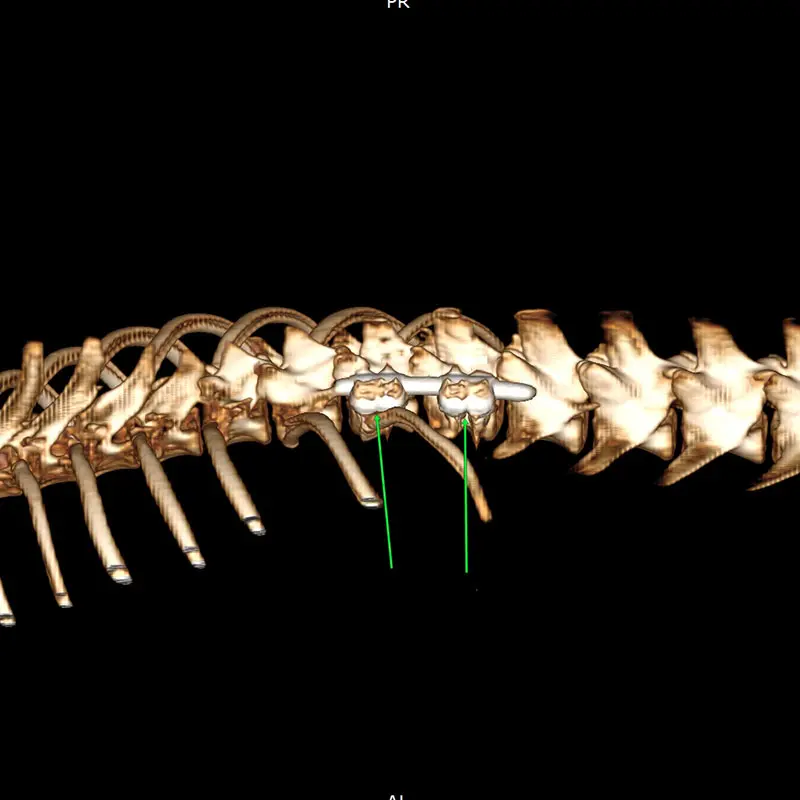

We have been using the system for years, and clinical experience greatly supports its reliability, even in difficult, challenging situations. It is excellent for stabilizing the spine, especially in the thoraco-lumbar region. If the connecting rod is placed ventrally from the articular processes, the screws are placed in the vertebral body at a 45-degree angle at the base of the transverse processes, so that they grip the largest possible bone material. (see CT images). Up to 2 clamps can be attached to a vertebral body from one side. Compared to other, more complex, multi-piece spinal stabilization systems, it is thinner and fits better on the surface of the bone. The screw axis is located ont he side of the axis of the connecting rod (the rod and the screw are not located on top of each other), the clamps can be rotated and slid, so that the largest possible bone stock can be freely accessed during surgery.

In our case, we stabilized the T13-L1 vertebral luxation of a 4-year-old dachshund, where the ligament system of the vertebral body was damaged during a car accident.